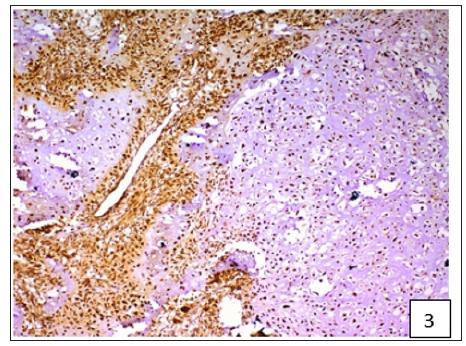

On the basis of histological classification of CMT, 26 cases were carcinomas, 20 carcinosarcomas and 7 sarcomas. Carcinomas were further classified into simple carcinoma (6/26), complex carcinoma (17/26), squamous cell carcinoma (2/26) and malignant myoepithelioma (1/26). The twenty cases of carcinosarcomas consisted of varying degree of epithelial, connective tissue and metaplastic components. Whereas, sarcomas comprised of 5 cases of osteosarcoma and one each of hemangiosarcoma and fibrosarcoma. Positive immunoreactivity of BCRP was observed in all the 53 cases of CMT. Diffuse and variable membranous and cytoplasmic immunoreactivity of BCRP was observed in cancerous epithelial cells and stromal connective tissue cells (Figures 1-3). The immunoreactivity of BCRP was also observed in endothelium, blood vessel wall, ductular epithelium and tumor emboli. On the basis of staining intensity, 7 cases revealed weak (+) immunoreactivity, 30 cases moderate (++) immunoreactivity and 16 cases strong (+++) immunoreactivity.

Figure 1:Diffuse and variable membranous and cytoplasmic immunoreactivity of BCRP was observed in cancerous epithelial cells and stromal connective tissue cells.

Figure 2:Diffuse and variable membranous and cytoplasmic immunoreactivity of BCRP was observed in cancerous epithelial cells and stromal connective tissue cells.

Figure 3:Diffuse and variable membranous and cytoplasmic immunoreactivity of BCRP was observed in cancerous epithelial cells and stromal connective tissue cells.